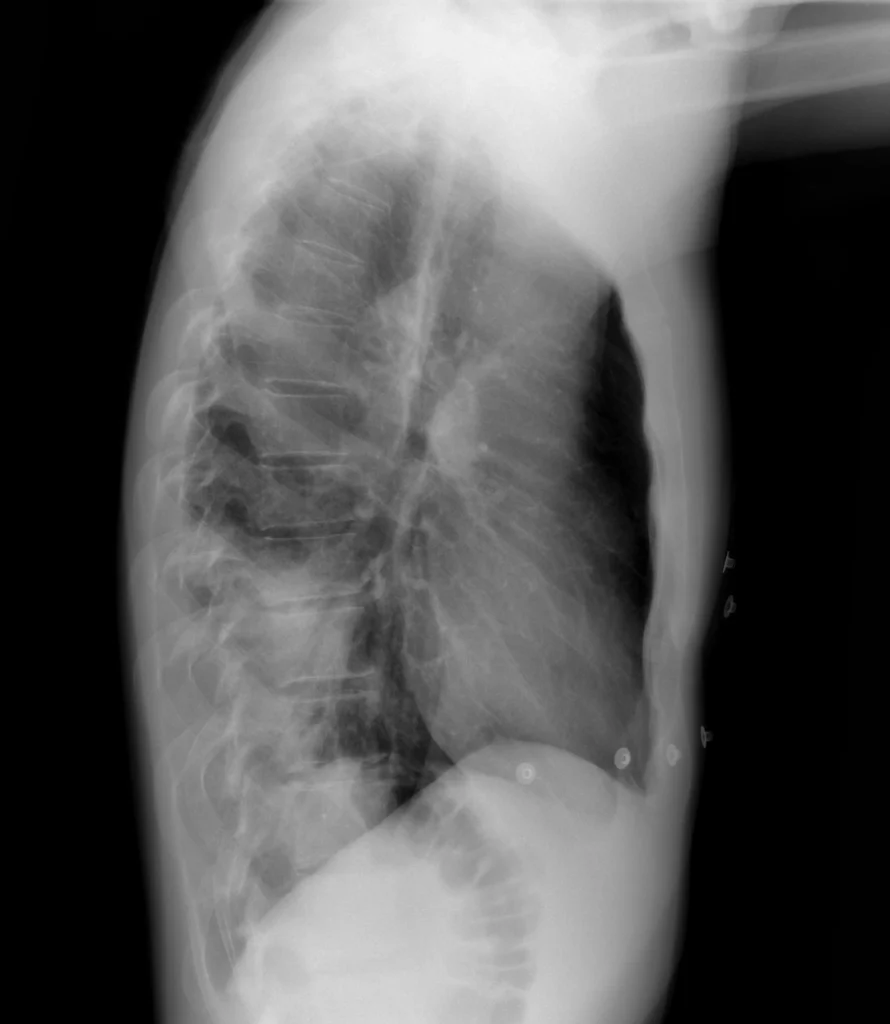

Rx de tórax LL. La opacidad se proyecta en el sector posteroinferior, confirmando la localización de la consolidación en el lóbulo inferior izquierdo, sugerida por el signo de la silueta negativo.

Opacidad del parénquima pulmonar con broncograma aéreo, en la proyección PA se observa en el tercio inferior del pulmón, en la proyección lateral ocupa el sector posteroinferior.

Otro signo radiológico qué se puede ver en la proyección lateral es el signo de la columna densa, por la suma de la densidad de la consolidacion. Normalmente los cuerpos vertebrales más distales deberían verse más radiolúcidos qué los proximales (mayor espesor de las bases pulmonares comparadas con los vértices).